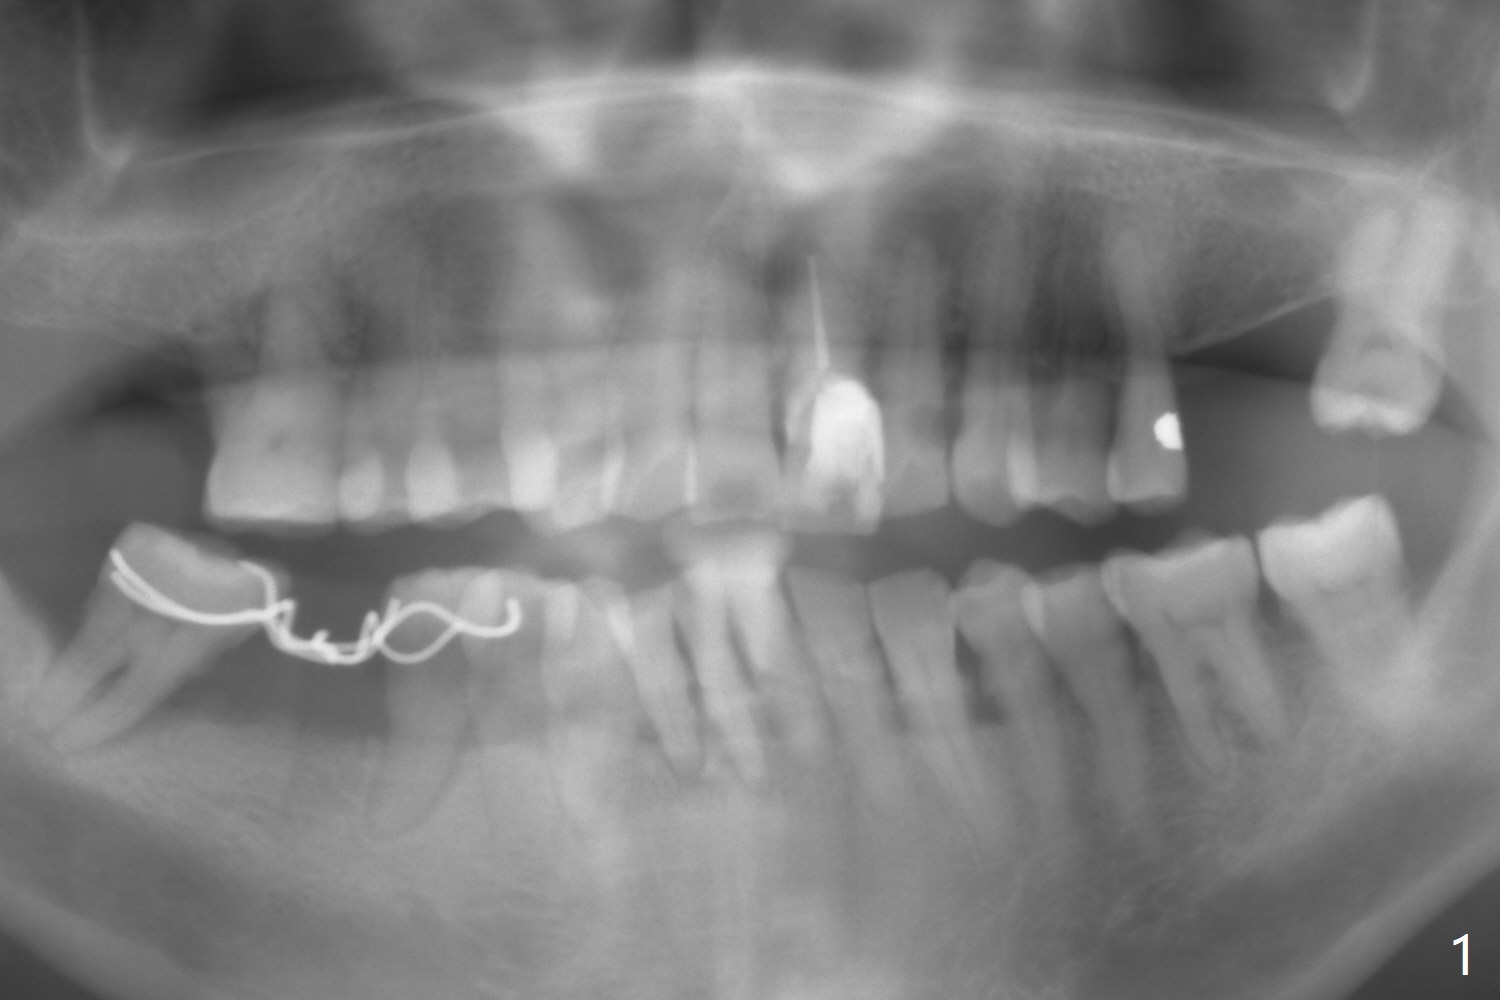

A 73-year-old man has poor dentition with lack of posterior support (Fig.1). The teeth #24-26 were mobile > 1 year ago (Fig.2), while the tooth #27 is reportedly now. To counter heavy mastication, long implants are to be placed (Fig.3). Take preop photos and PAs.